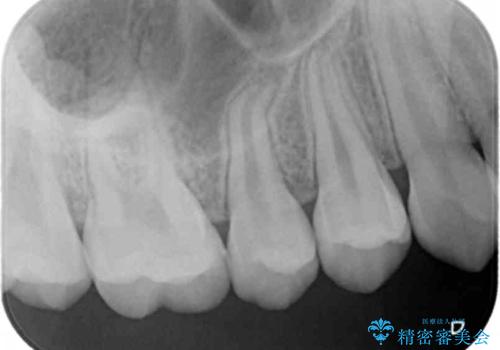

- 検査の結果、レントゲン画像上で虫歯が確認されたため治療をしていくこととなりました。

白くて精度の高いものをご希望されたためセラミックインレーでの治療を行いました。